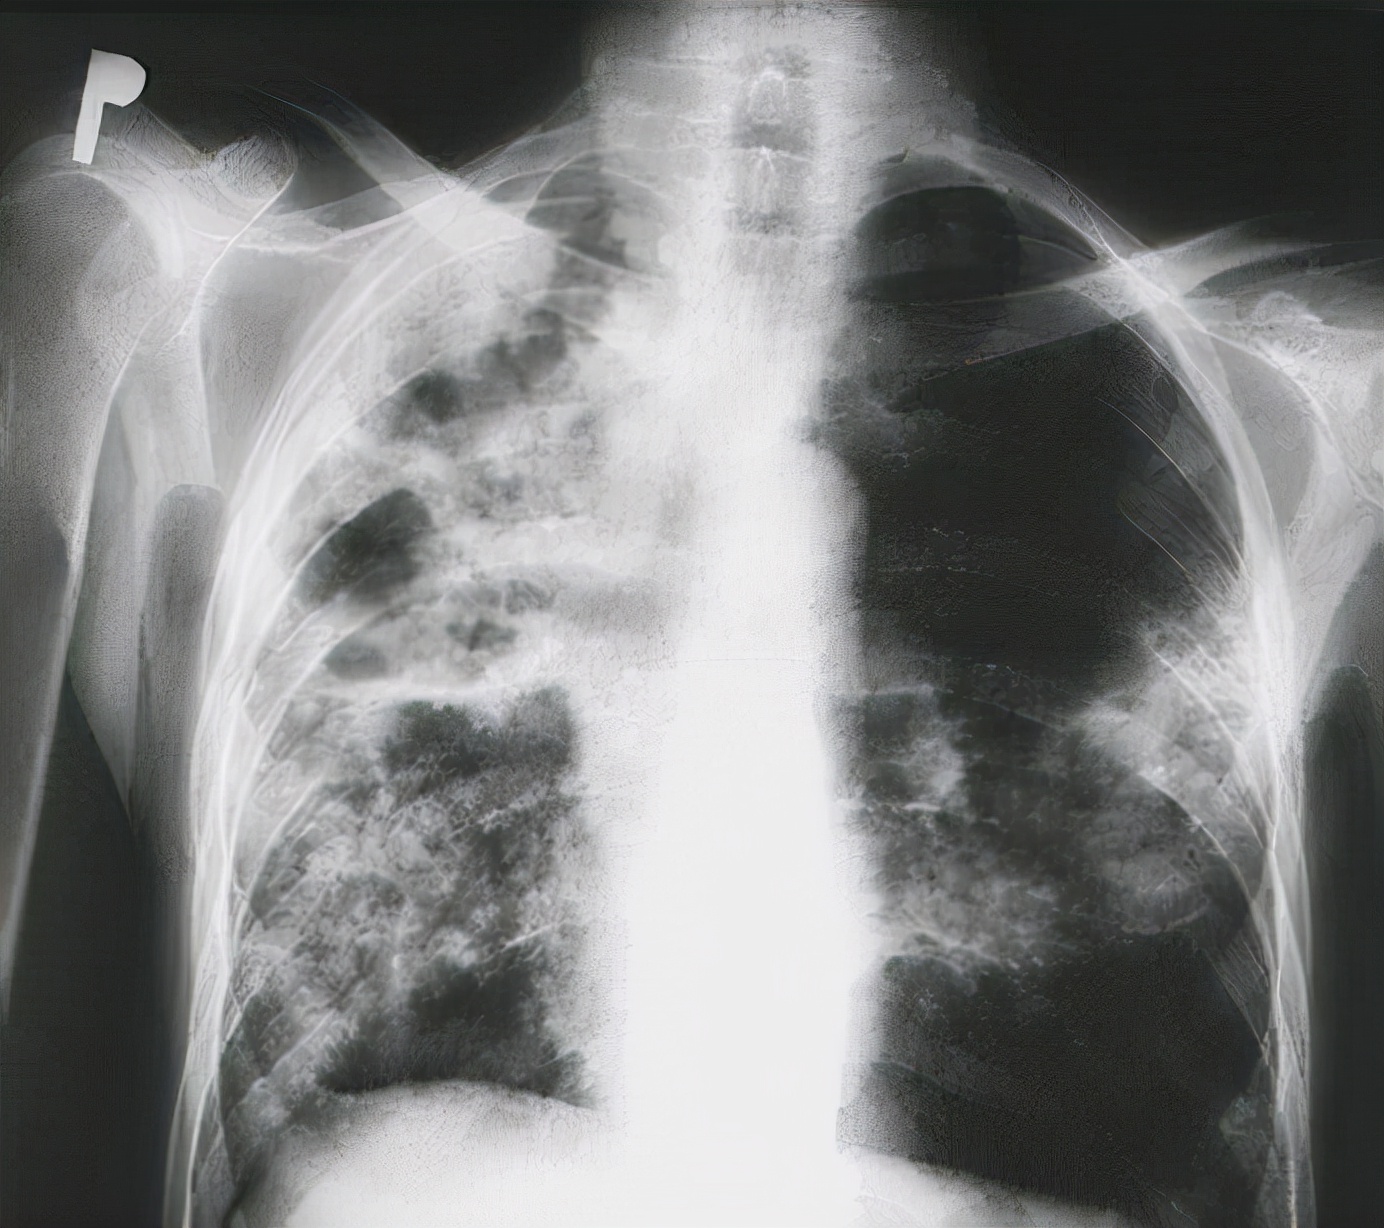

如果你注意观察 , 肺癌的发病率越来越高 , 有研究显示 , 在我们国家 , 肺癌已经成为发病率最高的癌症 。

这已经成为了我们国家居民的头号杀手 , 威胁着所有人的生命健康 。

肺癌的发病率居高不下 , 和以前相比 , 我们经常听到肺癌的名头 , 难道都是因为空气质量不好吗?

如果你真的觉得是空气的原因 , 那我只能说你理解得非常片面 , 其实肺癌的原因有很多 , 最重要的原因包括以下5个方面 。